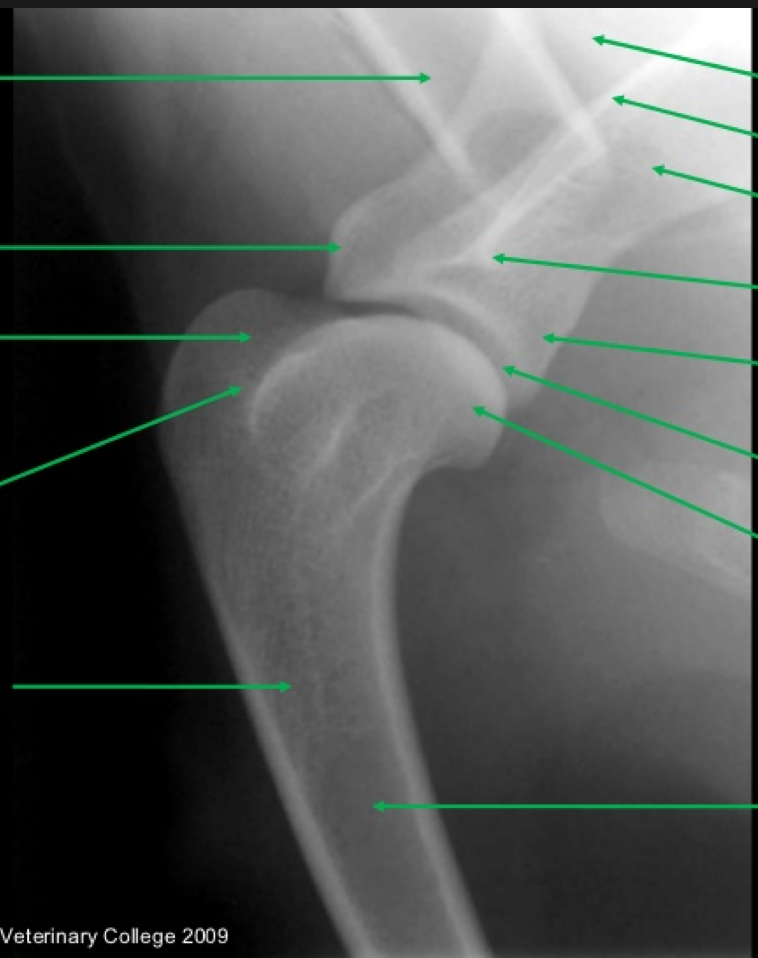

Patient number 244290 - Normal Canine Shoulder

WHICH PROJECTIONS ARE THESE?

Note the presence of an endotracheal tube within the trachea, which indicates the dog was

under general anaesthesia when the radiographs were taken. This facilitates accurate patient

positioning.

Note the relatively large joint space on the mediolateral projection. This is a non-weight

bearing exam and the width of the joint space depends on the amount of traction applied to the

limb for positioning.

Note the smooth contours of the joint surfaces of both the humeral head and the glenoid

cavity.

Mediolateral (ML) and caudocranial (CdCr) projections are provided.